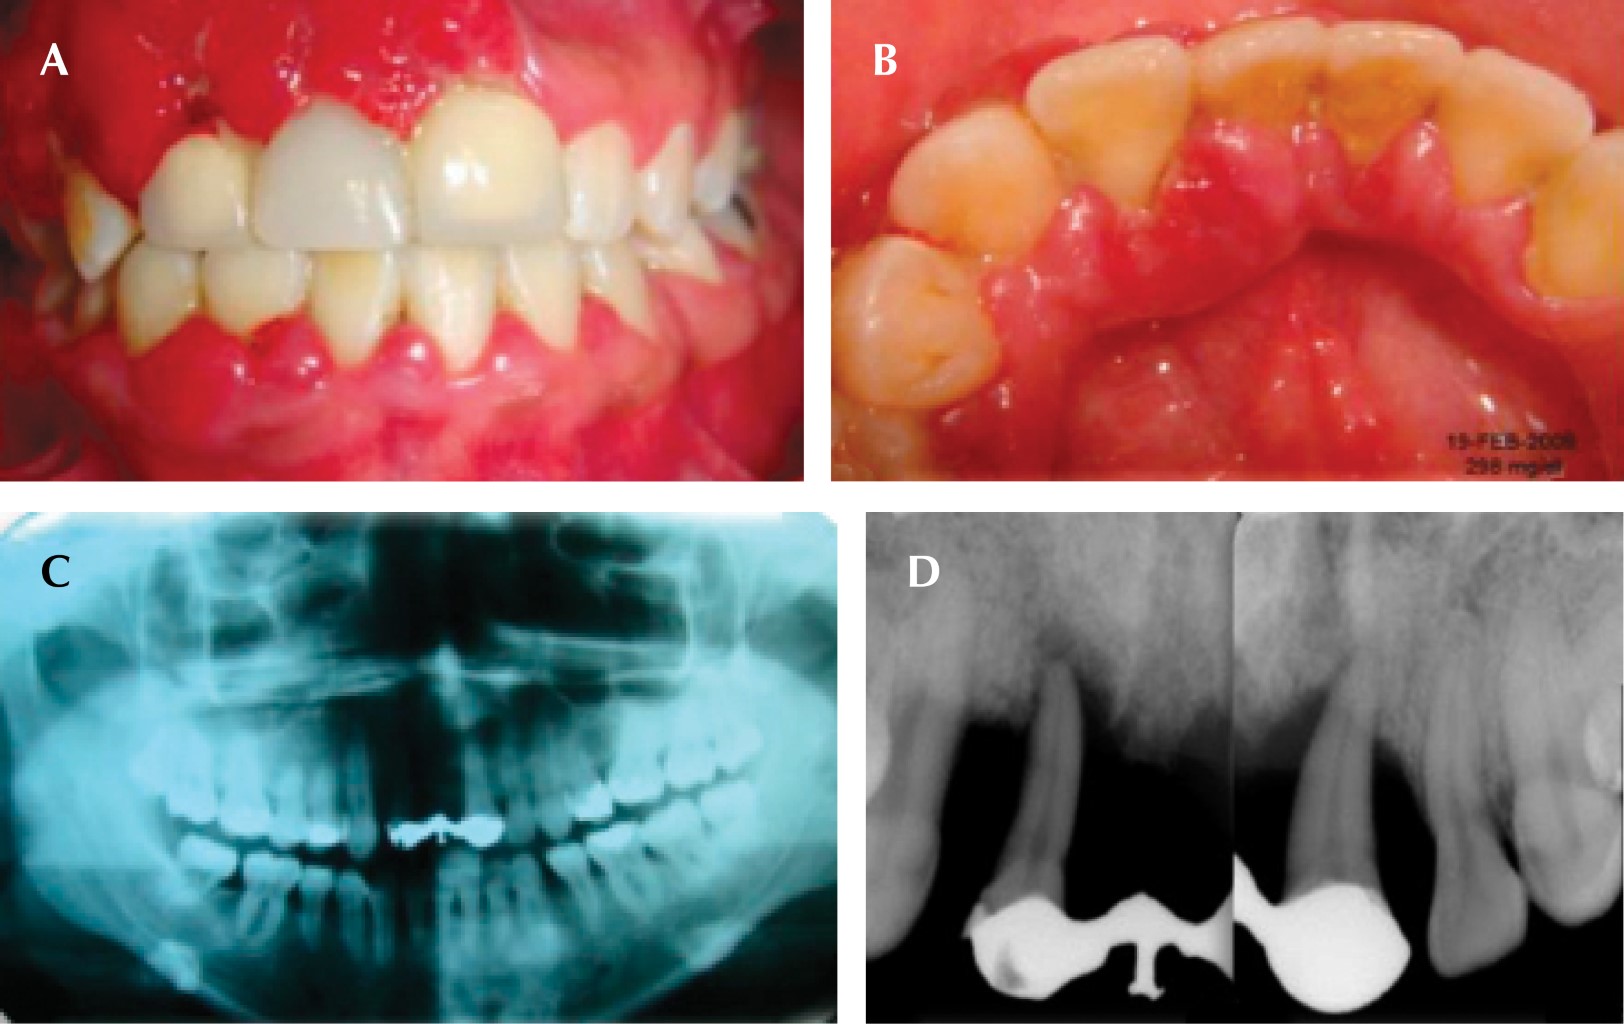

Se inició la fase I y con base en la adherencia al tratamiento periodontal y un adecuado seguimiento, a pesar de la renuencia de iniciar un tratamiento sistémico se obtuvo una respuesta favorable. El paciente abandona el tratamiento por dos años, a su regreso afirmó que ya es diabético e hipertenso, sometido a tratamiento a través de metformina y enalapril respectivamente. Por medio de radiografías panorámicas y la inspección clínica se observó mayor pérdida ósea generalizada, lo cual mostró la progresión de la enfermedad periodontal, debido al desapego al tratamiento y la suma del factor sistémico (Figura 7A y B). Se inició (nuevamente) la fase I periodontal, realizando múltiples extracciones, debido a las condiciones en las que se presentó. Posteriormente se rehabilitó por medio de una prótesis parcial removible provisional inmediata (Figura 8A y B).